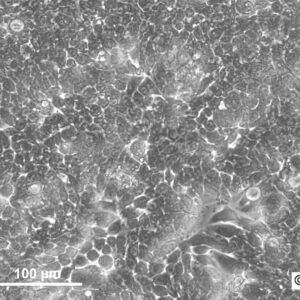

Morphology: Epithelial-like

Growth Properties: Adherent

Description: HuH7 was established in 1982 by Nakabayashi et al. from a 57-year-old Japanese male with well differentiated hepatocellular carcinoma.